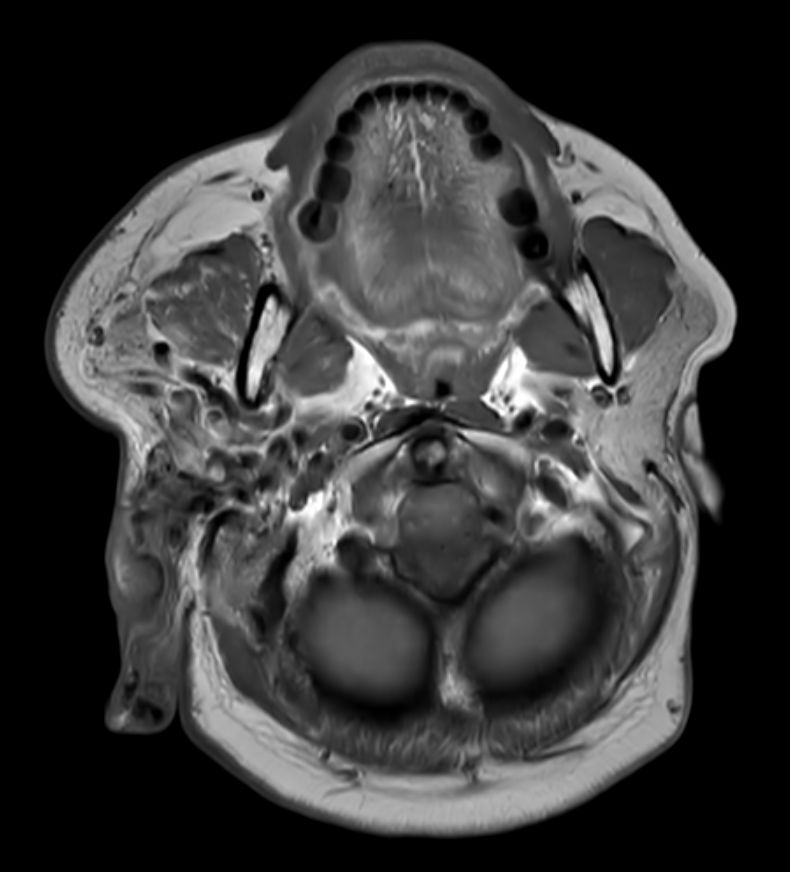

T1w TSE Compressed SENSE